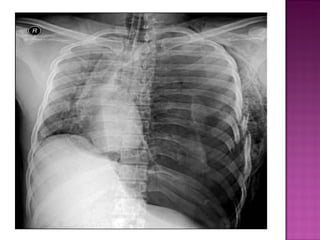

NEUMOTORAX A TENSION MANIFESTACIONES CLINICAS Y TRATAMIENTO DOLOR TORACICO FALTA DE AIRE DIFICULTAD RESPIRATORIA TAQUICARDIA HIPOTENSION TRAQUEA DESVIADA AUSENCIA DE M.V DISTENCION DE VENAS DEL CUELLO CIANOSIS  EL DIAGNOSTICO ES CLINICO - RADIOLOGICO DESCOMPRESION  INMEDIATA

NEUMOTORAX A TENSIONMANIFESTACIONES CLINICAS Y TRATAMIENTO DOLOR TORACICO FALTA DE AIRE DIFICULTAD RESPIRATORIA TAQUICARDIA HIPOTENSION TRAQUEA DESVIADA AUSENCIA DE M.V DISTENCION DE VENAS DEL CUELLO CIANOSIS EL DIAGNOSTICO ES CLINICO - RADIOLOGICO DESCOMPRESION INMEDIATA